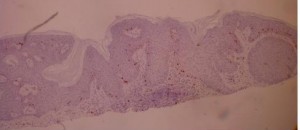

ki-67 staining of reticulo-acanthotic type of SKs.

ki-67 staining of reticulo-acanthotic type of SKs.

Ki-67 staining of an acantho-hyperkeratotic type of SK. On the last picture, most of the basal staining comes from the accumulation of pigment as the clinical image suggests.

Ki-67 staining of an acantho-hyperkeratotic type of SK. On the last picture, most of the basal staining comes from the accumulation of pigment as the clinical image suggests.

ki-67 staining of reticulo-acanthotic type of SKs.

ki-67 staining of reticulo-acanthotic type of SKs.

Ki-67 staining of an acantho-hyperkeratotic type of SK. On the last histological picture, most of the basal staining comes from the accumulation of pigment as the clinical image suggests.